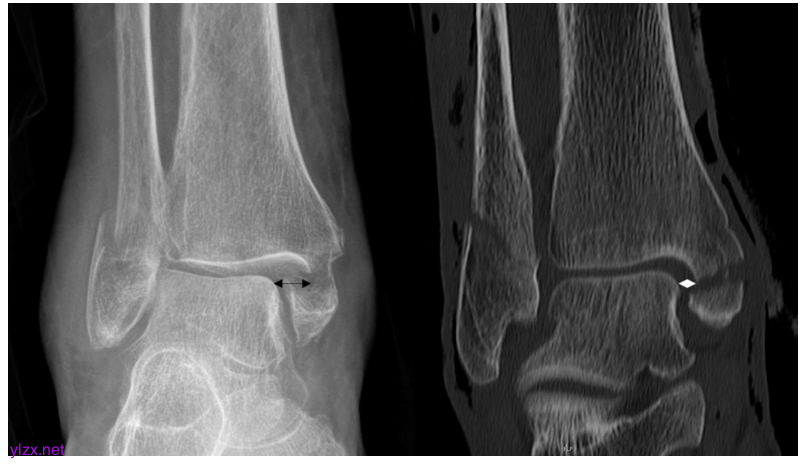

三踝骨折的前后位X线片。

左图显示了处于预还原状态的脚踝。黑色箭头显示内侧间隙扩大到8.3毫米。右图显示计算机断层扫描中踝关节后复位。白色钻石显示测量的内侧间隙为4.2毫米